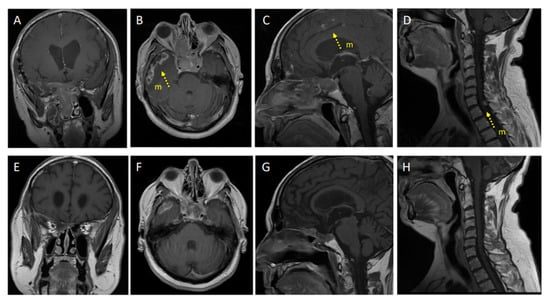

2. Clinical Observation: Efficacy of Pembrolizumab in A Metastatic Non-Functioning PitNET

| Feola, 2022 [this report] | 57, M Case 13 | Pit-1 non-functioning metastatic PitNET (Hormone negative) | SNC and dural | NS (3 times); RT (2 times sellar + metastases); TMZ (5 cycles+ metronomic schedule). | Pembro (200 mg) every 21 days. | Ki-67 10%, p53 < 5% (NS 1/2); Ki67 20%, p53 10%, M = 1/10 HPFs (NS 3). | Primary: MGMT promoter unmethylated; PDL1 IHC pos (95%); MSH2/6 IHC pos; CD68 > CD4 > CD8 IHC pos. TIL 1 |